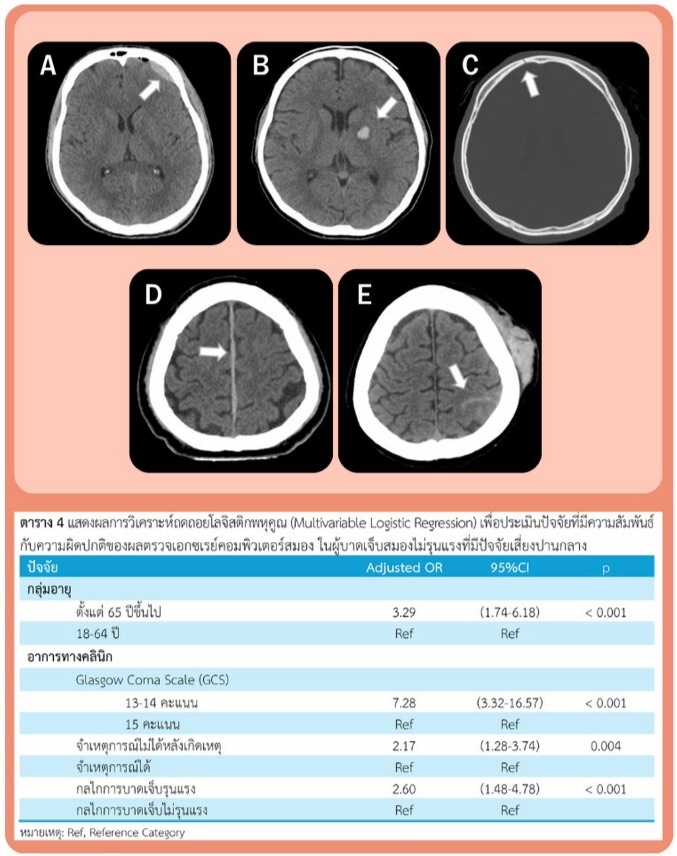

ปัจจัยที่มีความสัมพันธ์กับความผิดปกติของผลตรวจเอกซเรย์คอมพิวเตอร์สมอง ในผู้บาดเจ็บสมองไม่รุนแรงที่มีปัจจัยเสี่ยงปานกลาง ที่โรงพยาบาลทุ่งสง

กอกานต์ อนันตทวีกุล

e6984